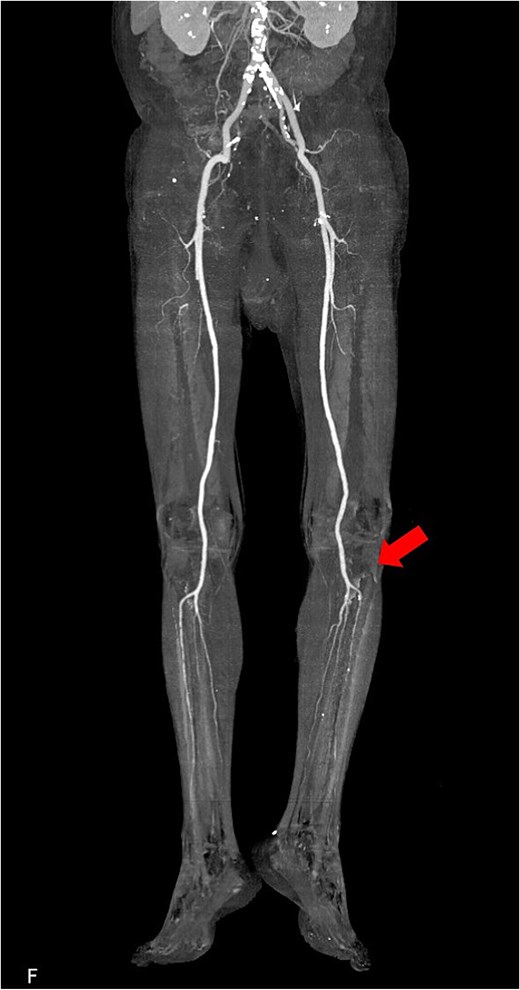

The patient was a 78-year-old man who had been hospitalized at a prior institution for Tolosa-Hunt syndrome, a rare inflammatory condition causing orbital pain. He had undergone steroid pulse therapy and was maintained on oral prednisolone (40 mg daily). He was also receiving medical treatment for diabetes mellitus, with an HbA1c level of 7.9%. The patient presented with complaints of left leg discomfort and weakness. Contrast-enhanced CT revealed poor perfusion distal to the left common iliac artery, leading to a diagnosis of ALI. He was subsequently transferred to our surgical department for further evaluation and treatment. On arrival, physical examination revealed coldness in the left lower limb, with absent palpable pulses in the dorsalis pedis and posterior tibial arteries. Doppler ultrasonography confirmed the absence of arterial flow in the left lower extremity, consistent with critical ischemia. The patient's electrocardiogram showed sinus rhythm. A review of CT imaging showed thrombotic occlusion extending from the left common femoral artery (CFA) to the superficial femoral artery, with poor perfusion distal to the popliteal artery (Video 1) (Fig. 1). Additionally, a filling defect was identified in the distal aortic arch, consistent with a thrombus (Fig. 2a). The thrombus appeared pedunculated and was attached to the lesser curvature of the descending thoracic aorta distal to the left subclavian artery. It was considered highly mobile, posing a significant risk of embolization. No evidence of intracardiac thrombi was observed, and the DTAT was identified as the likely embolic source responsible for the ALI. Given the urgency of salvaging the ischemic limb, thrombus retrieval was prioritized, while simultaneous management of the embolic source was deemed equally critical to prevent recurrence. Open surgery was considered high-risk due to the patient’s age, diabetes, and chronic steroid use. As a less invasive alternative, we opted for TEVAR to immobilize the floating thrombus. During the procedure, bilateral CFAs were surgically exposed to provide access and enable immediate removal of the embolic source if needed. A transesophageal echocardiogram (TEE) revealed a highly mobile intra-aortic thrombus (Video 2). A 26× 26 × 150 mm stent graft (Valiant Captivia Thoracic Stent Graft; Medtronic, Santa Rosa, CA, USA) was deployed just distal to the left subclavian artery under fluoroscopic guidance. Real-time TEE guidance ensured continuous monitoring of the floating thrombus and confirmed no embolization during intravascular manipulation. Following stent graft deployment, thrombus retrieval was performed via the left CFA using a 4-Fr Fogarty catheter (Fogarty Fortis arterial embolectomy catheter; Edwards Lifesciences, Irvine, CA, USA), successfully retrieving fibrin thrombi. Intraoperative angiography demonstrated restored blood flow in the lower extremity, with improved perfusion extending to the foot. Pulses in the dorsalis pedis and posterior tibial arteries were palpably restored bilaterally. The patient was extubated in the operating room and progressed without any findings suggestive of intestinal or lower extremity ischemia. Postoperative CT confirmed successful exclusion of the aortic thrombus (Fig. 2b) and restoration of adequate lower limb perfusion (Fig. 3). The patient was initiated on oral anticoagulation therapy with edoxaban 30 mg to prevent future thrombus formation and experienced an uneventful recovery. This patient has remained free of recurrent embolic events and has shown stable progress post-procedure.

Postoperative 3D reconstructed contrast-enhanced CT. The contrast effect on lower limb blood flow is good.